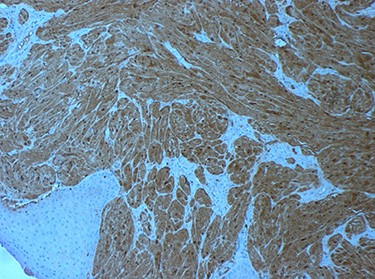

tumour cells staining positive for S-100 on immunohistochemistry.

Macroscopically, the final specimen demonstrated a white submucosal epiglottic nodule (Fig. 8). Immunohistochemistry showed GCT (strongly positive for S-100 protein and weakly positive for CD68). Microscopically, tumour cells had abundant granular cytoplasm that was periodic acid-Schiff (PAS) positive and diastase resistant; these cells were closely associated with some nerve fibres. The tumour abutted the epiglottic cartilage. The closest margin was <1 mm inferiorly with good clearance (≥3 mm) at other mucosal margins. There was no evidence of necrosis, atypical mitoses or increased mitotic activity.